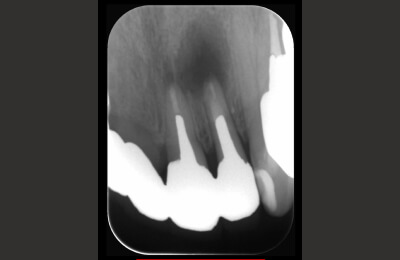

精密根管治療症例

-

術前

治療中

矢印部が処置されていない

術後

| 主訴 | 噛むと違和感がある。 レントゲンで根の先に黒い影を指摘された。 |

|---|---|

| 治療期間 | 根管治療3回 補綴治療3回 |

| 治療費 |

(ファイバーコア・ジルコニアクラウン) |

| 治療内容 |

通法の根管治療を行いました。ラバーダム防湿、 マイクロスコープ下で未処置であった根管を発見し処置。 |

| 治療のリスク |

治療直後は反応性に一時的な腫れや痛みが出る可能性があります。 根管治療で改善が見られない場合は外科的根管治療が必要になる場合があります。 |